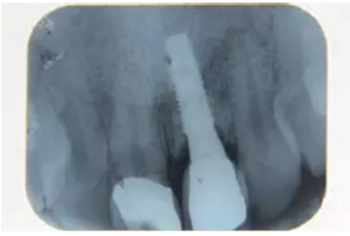

種植完成后可以通過拍攝曲面體層或是根尖片來確認(rèn)種植體的植入情況,并作為資料加以保存。

圖7 曲面體層片